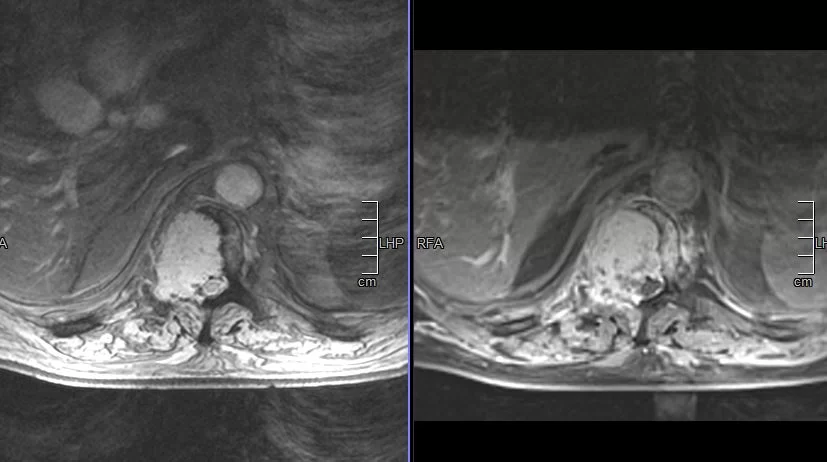

Παράδειγμα εξωσκληρίδιου όγκου: Ασθενής Άρρεν, 73 ετών, με γνωστή μεταστατική μάζα στον Θ10 σπόνδυλο, η οποίοα προκαλεί σημαντική στένωση του σπονδυλικού σωλήνα και πίεση επί του νωτιαίου μυελού. Διενεργήθη αποσυμπίεση του νωτιαίου μυελού και διαδερμική σπονδυλοδεσία/σπονδυλοπλαστική Θ9-Θ10. Μετεγχειρητικά ο ασθενής ανέφερε σημαντική πίεση του άλγους του και σημαντική βελτίωση της βάδισης.

(Προσωπικό Αρχείο Νευροχειρουργού Π. Σταυρινού)